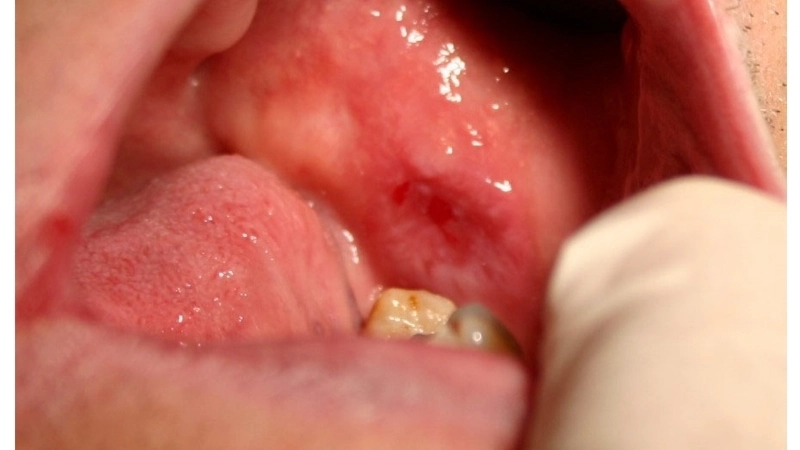

• Trên niêm mạc miệng, lichen phẳng ở miệng thường có dạng lưới màu trắng, có thể gây đau rát, đặc biệt khi ăn thức ăn cay nóng.

Biểu hiện lichen phẳng ở miệng với các vết loét